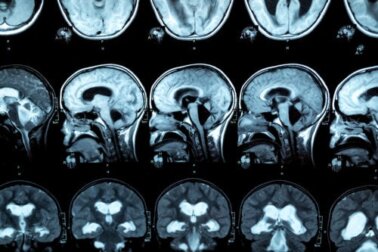

Para o diagnóstico desta patologia , é realizada uma ressonância magnética, para que possam ser observadas as lesões no corpo caloso. Nesse sentido, pesquisas indicam que pessoas com transtorno por uso de álcool apresentam redução da espessura anterior, média e posterior do corpo caloso, bem como variações no tamanho do lobo frontal e dos sulcos corticais.

Caracteriza-se por desmielinização, bem como eventual necrose, do corpo caloso. O que significa isto? O corpo caloso é uma estrutura localizada no cérebro que conecta os dois hemisférios, ajudando ambos a trabalharem de forma coordenada.

O inchaço do corpo caloso também pode ser observado nas imagens do cérebro. Em alguns casos, sinais de síndrome de desconexão inter-hemisférica estão presentes.